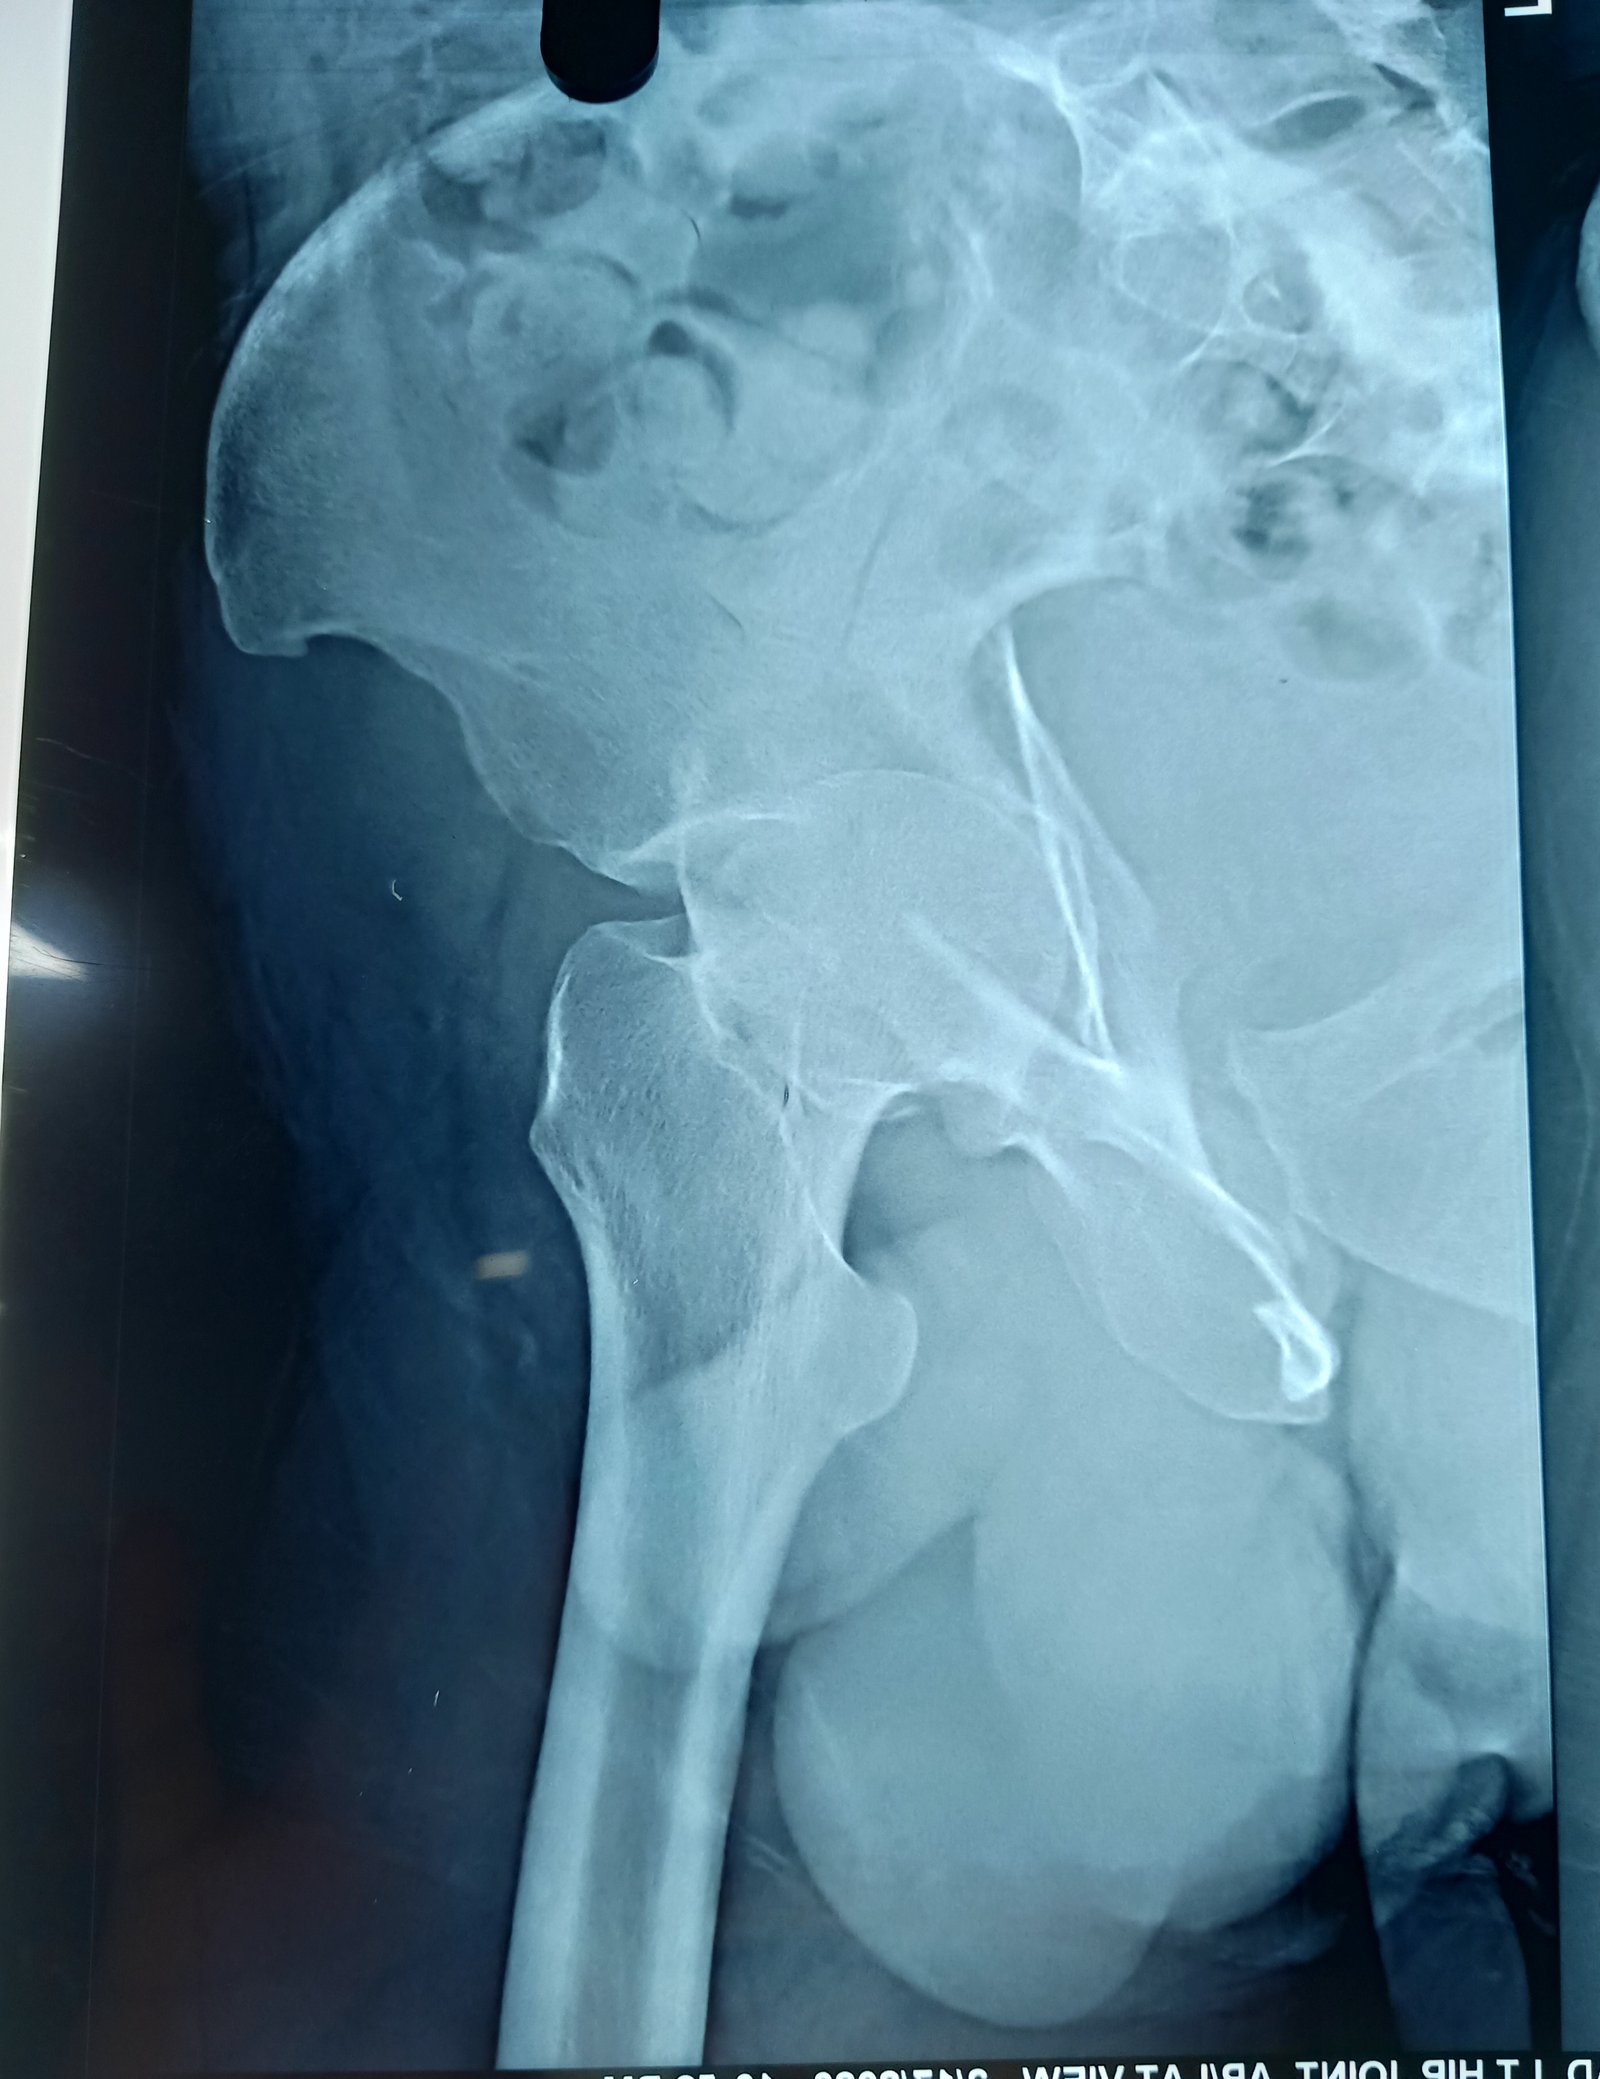

acetabulum

anterior collumn of acetabulum fixation done via anetrior appoach